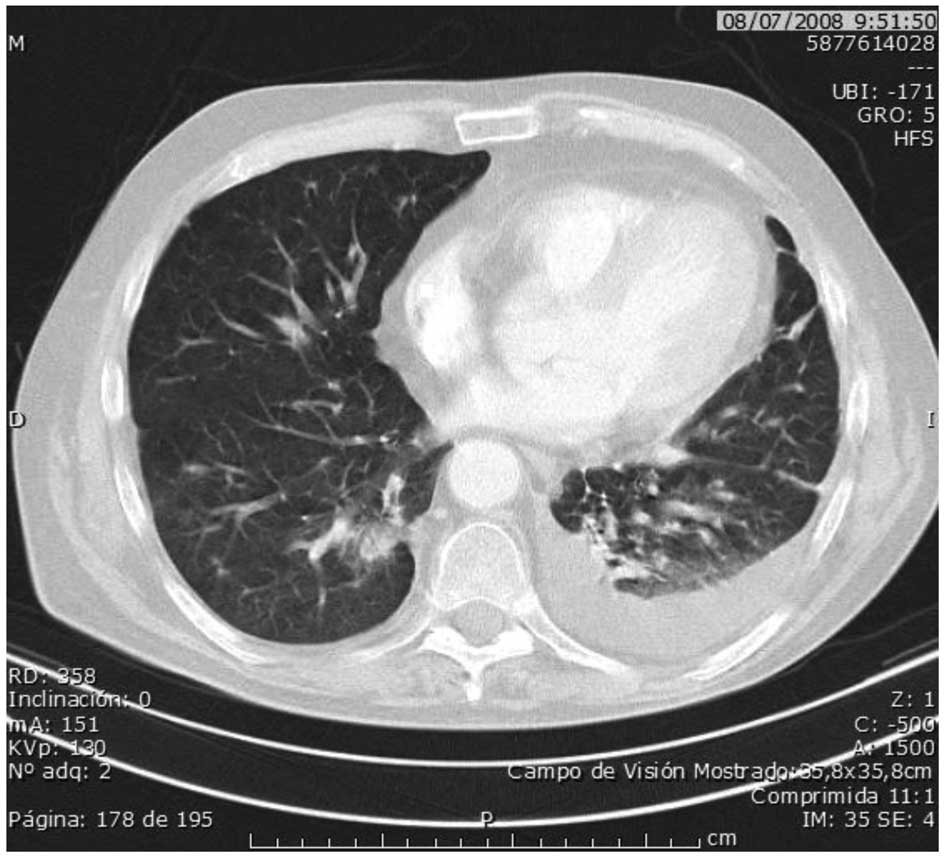

Figure 2

July 2008: The CT scan revealed new pulmonary nodules and pleural effusion.